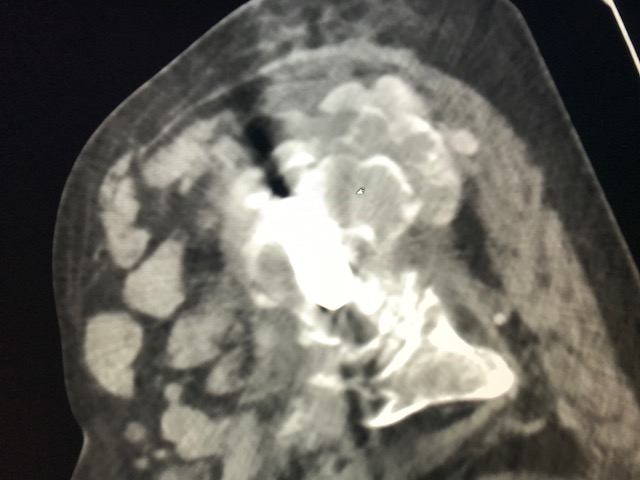

Figure 1 for case Tumoral calcinosis ( RID5202 )

Figure 1

Tumoral calcinosis likely, given hypercalcemia, peritoneal dialysis catheter, lack of lymphocytosis on the aspiration and lack of soft tissue changes; really points away from pseudotumor AVAL ATR.

Tumoral calcinosis ( RID5202 )